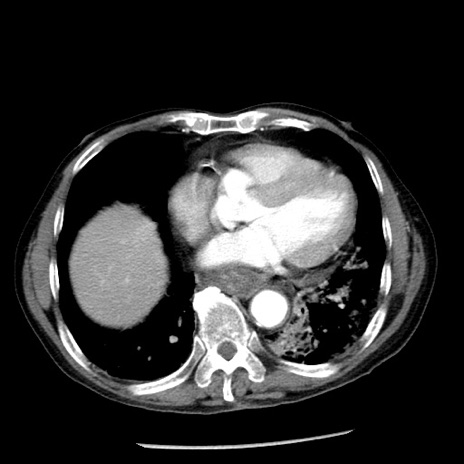

症例26(横断像)

【症例】80歳代男性

【主訴】嘔吐

【現病歴】昨晩2回嘔吐あり、今朝になっても嘔吐あり。来院。

【既往歴】胃潰瘍

【身体所見】意識清明、BT 37.6℃、BP 166/95mmHg、HR 100bpm、SpO2 97%、腹部:平坦・軟、腸蠕動音聴取良好、圧痛なし。

【データ】WBC 21900、CRP 1.46